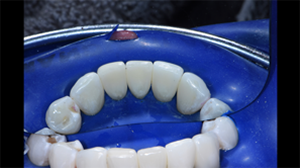

Fig. 2: Rubber dam isolation is done for best field control and soft tissue retraction. Following isolation, the teeth are dried and disclosing solution applied once to reveal biofilm. Biofilm is subsequently removed with aluminum trihydroxide in a Bioclear Bioblaster. Rubber cup and pumice is inadequate for removal of biofilm in the interproximal spaces, which are areas critical for strong adhesion and effective closure of black triangles.

Fig. 3: Black Triangle Kit small incisor matrices placed. Tooth #24 is to be injection molded first. All matrices are preselected using the Black Triangle Gauge prior to rubber dam isolation. The mix of matrices was chosen to adequately close the spaces and maintain vertical contacts without canting.

Fig. 4: Lingual view with matrices placed to show the change in tooth contour that will be obtained to achieve adequate space closure.